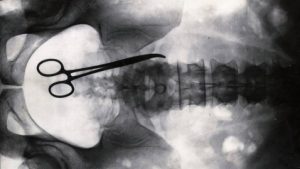

Terrifying Tales Of Medical Malpractice

ht_scissors_xray_ll_121220_wblog